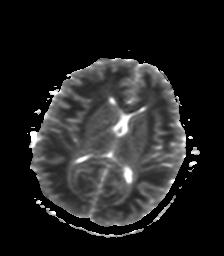

发热、头痛伴精神异常1周

脑炎,肾上腺性脑白质营养不良待除外

较对称性脑白质异常信号,深部白质t2明显低信号(铁质沉积过多?)

考虑脑白质病变,请结合临床病史及实验室检查进一步分析。